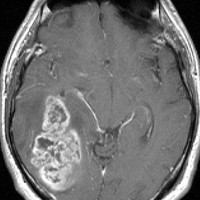

典型的な膠芽腫のガドリニウム増強画像です。右の側頭葉から発生したために目立った症状が無く,この大きさで発症しました。何となくボッとしていると言うのが訴えでした。腫瘍の周囲がガドリニウムで白く増強されて,内部は壊死で低信号(黒っぽい)になっています。